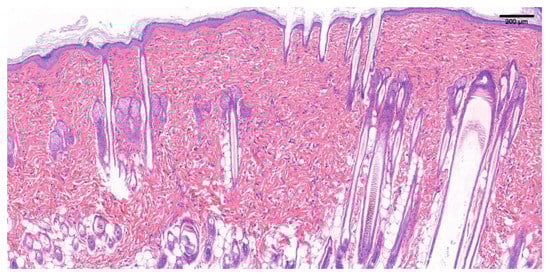

3.5.1. SD Rat Normal Skin Tissue Section

3.5.2. H&E Staining of Newborn Tissue Sections of Damaged Wounds in SD Rats